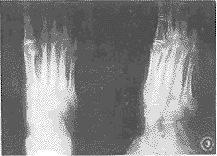

2.1 X线表现(图1~3):

图1 左足跗骨及第二、三、骨弥漫性骨质破坏,骨干粗细不均匀,跗骨间关节亦受侵犯。软组织肿胀

, http://www.100md.com

图2 右足跗骨骨质破坏,并可见骨质硬化

图3 右足软组织肿胀,第三、四骨近端骨质破坏,骨皮质凹凸不平

2.1.1 软组织弥漫肿胀占100%。其中8例见软组织有稍高密度结节影(均为临床软组织呈结节性肿胀者)。

2.1.2 软组织内见低密度之窦道影。

2.1.3 足骨改变:无骨质改变者11例,单纯骨皮质侵蚀14例,皮质、髓质破坏者75例,有死骨形成者5例。骨增生硬化改变48例,骨干增粗畸形者40例,骨膜反应18例,单骨破坏者26例,多骨破坏者65例。

3.3 X线表现:①软组织肿胀,在重点显示软组织的X线片上可见稍高密度类似生姜样的结节状改变(病理为霉菌性肉芽肿形成);②骨破坏是由周围软组织感染直接蔓延而来,故骨破坏的次序是先皮质后髓腔,可有皮质局限性破坏,皮质、髓腔广泛溶骨性破坏等表现形式。③死骨少见,④足骨间关节及多骨受累为其特征。⑤病程长的病例可见骨增生硬化及骨干增粗等骨修复表现。作者认为该病与一般慢性骨髓炎有相似改变,但骨破坏始终呈进行性,与骨修复相比,骨破坏始终占优势,该点也被病理检查所证实。